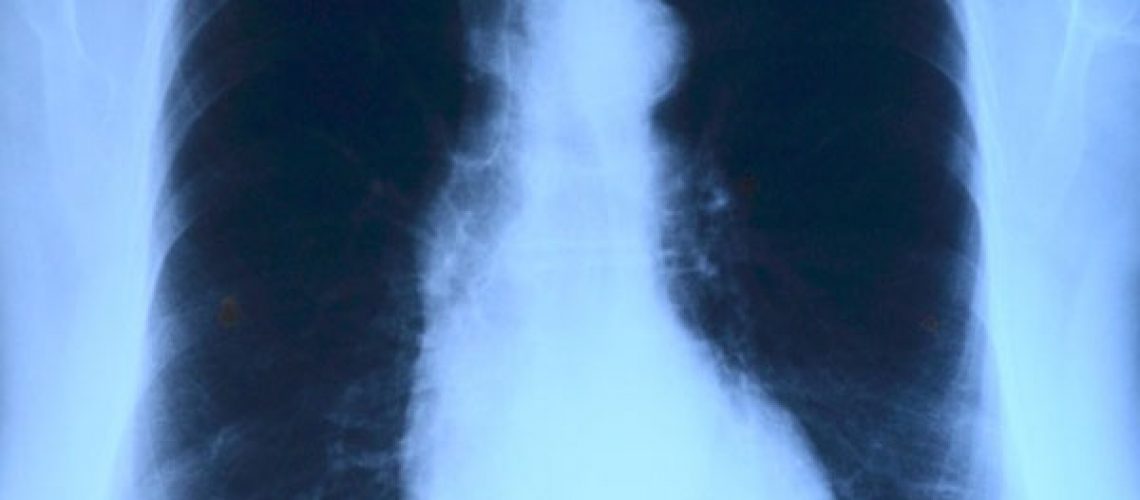

There are many different symptoms to mesothelioma due to the fact that there are different forms of the cancer. Some of the symptoms include shortness of breath, painful coughing, pain under the rib cage, abdominal swelling, unusual lumps of tissue under the skin on your chest or stomach, unexplained weight loss, and more. It is always important to report any concerning symptoms to your doctor right away, especially if you believe you may have been exposed to asbestos. Remember that it can take decades for mesothelioma to develop after your exposure, so there may always be a chance that your disease was work related.